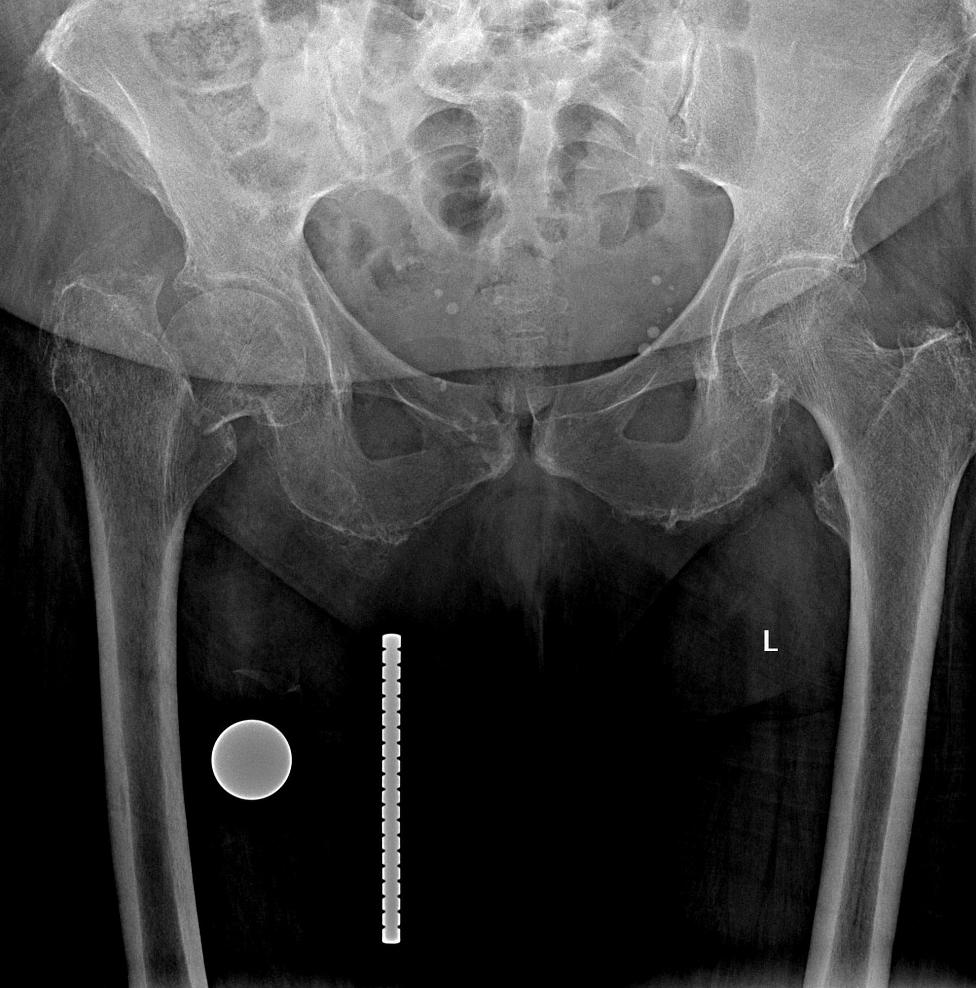

Перелом Бедра Фото Рентген

Перелом Бедра Фото Рентген 138 фото